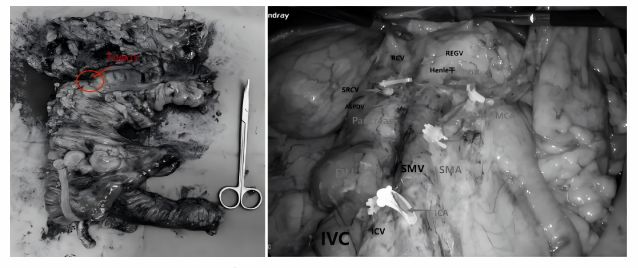

经过四个疗程的靶向+化疗治疗,在第2次评估时,影像报告让所有人振奋——双肺转移灶完全消失,原发肠癌病灶明显缩小,肿瘤指标趋近于平衡。抓住治疗窗口期,陈洪生教授团队为患者实施腹腔镜右半结肠癌根治术,膜解剖理念下D3清扫,精准切除病灶及周围淋巴结,术后病理分期pT2N1M0,肿瘤已缩小到直径不足1cm,周围淋巴结转移1/32。围手术期贯彻ERAS理念,个体化管理,早期离床活动、恢复胃肠道功能,患者术后1周顺利康复出院,择期来院继续进行术后的辅助抗肿瘤治疗,我们有充足的信心,患者会有一个良好的预后。